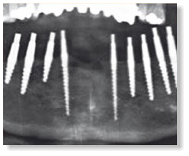

Totale Unterkiefer Versorgung

mit insgesamt 10 Champions

und einer einteiligen,

vollverblendeten

Zirkondioxid-Brücke.

Nach einer Woche post OP erfolgte

die Gerüstanprobe und

zweite Bissnahme, nach weiteren

vier Tagen das definitive

Einzementierender verblendeten

Suprakonstruktion mit Fuji IX.

Die minimal-invasive Methodik

der Implantation („MIMI“) kam

auch hier zur Anwendung - die

Pfeiler - Divergenzen habe ich

mit Präparationen während der

Gerüstanprobe ausgeglichen.

Ausgeprägte Höcker- Fissuren-

Reliefs sind bei der

Keramikschichtung

auf dem

spannungsfreien Gerüst zu

vermeiden.